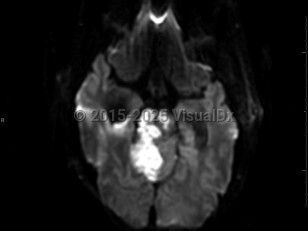

Brain stem stroke

A brain stem stroke involves the brain stem, which is composed of the midbrain, pons, and medulla oblongata. Symptoms are typically acute in onset and depend on the location of injury but may include cranial nerve dysfunction resulting in eye movement abnormalities, diplopia, facial weakness or sensory loss, vertigo or dizziness, dysarthria, dysphagia, and/or tongue deviation. There may be decreased level of consciousness, abnormal breathing, nausea, body weakness, imbalance, or coordination problems as well. There are several named syndromes characterized by location of the stroke and resulting symptoms; locked-in syndrome is the most serious. Prognosis depends on the location and size of the stroke as well as timely evaluation and treatment. The brain stem gets its blood supply largely from the posterior circulation (vertebrobasilar system) with little collateral supply.